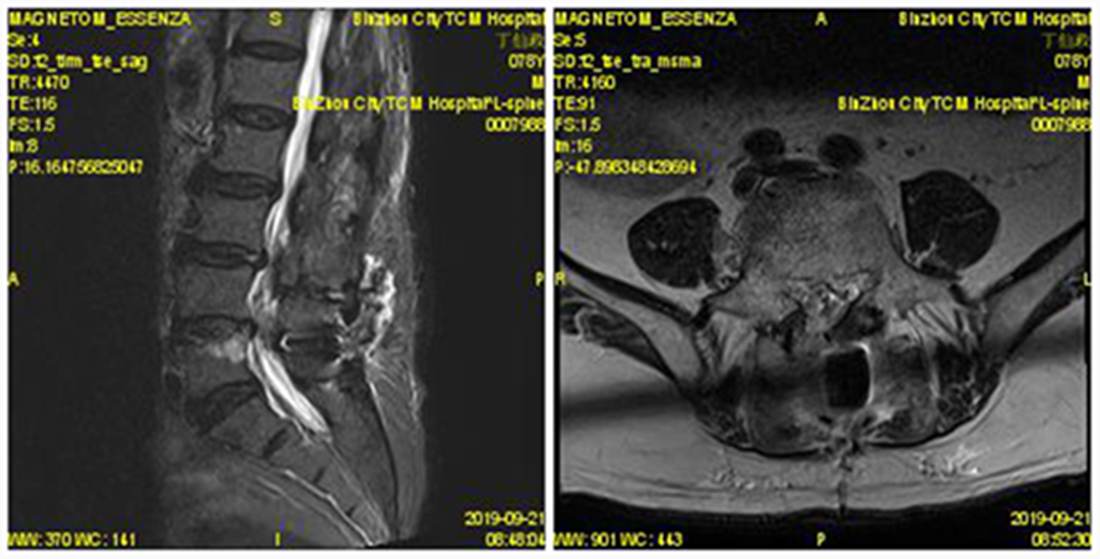

入院后经过详尽询问病史、仔细查体及全面影像检查及分析。患者存在腰部脊椎的纵向的失稳,在站立时存在椎间隙变窄,椎间盘组织进一步突出明显。针对此病患的传统理念,是行腰椎椎弓根螺钉固定加以椎间隙植骨融合术治疗,但由于该患者年龄较大,若以传统理念进行手术,对此高龄患者的创伤较大,恢复期较长。综合考虑后,决定为该患者采取椎板开窗髓核摘除术加以棘突间动态固定(COFLEX)术。

术前MRI

术后MRI